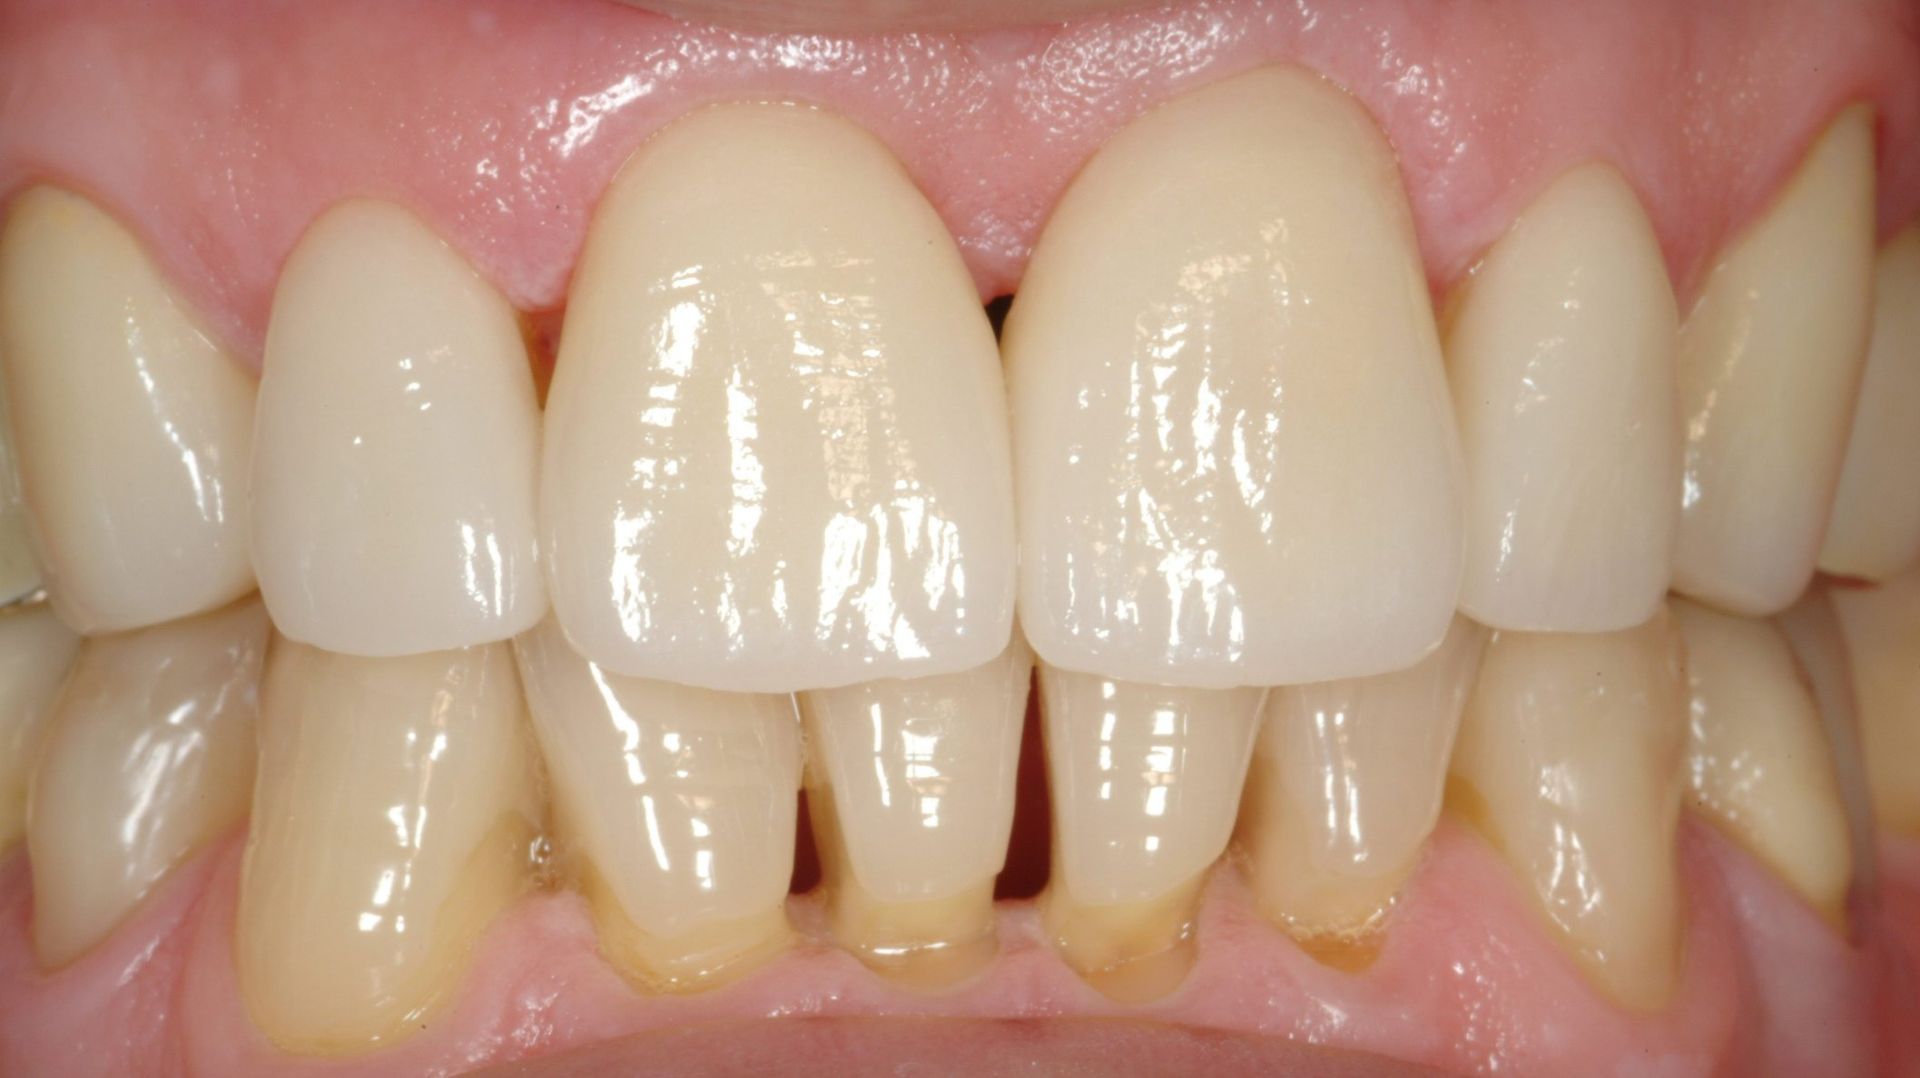

Faccette in ceramica

Le faccette in ceramica sono sottili lamine personalizzate che vengono applicate sulla superficie anteriore dei denti per migliorare l'estetica del sorriso. Questi dispositivi sono ideali per correggere imperfezioni come macchie, scheggiature, denti disallineati o spazi eccessivi. Le faccette in ceramica offrono un risultato naturale e duraturo, grazie alla loro resistenza e alla capacità di imitare l'aspetto dei denti naturali. Lo studio garantisce un'applicazione precisa e personalizzata, adattando le faccette alle esigenze estetiche e funzionali di ogni paziente.